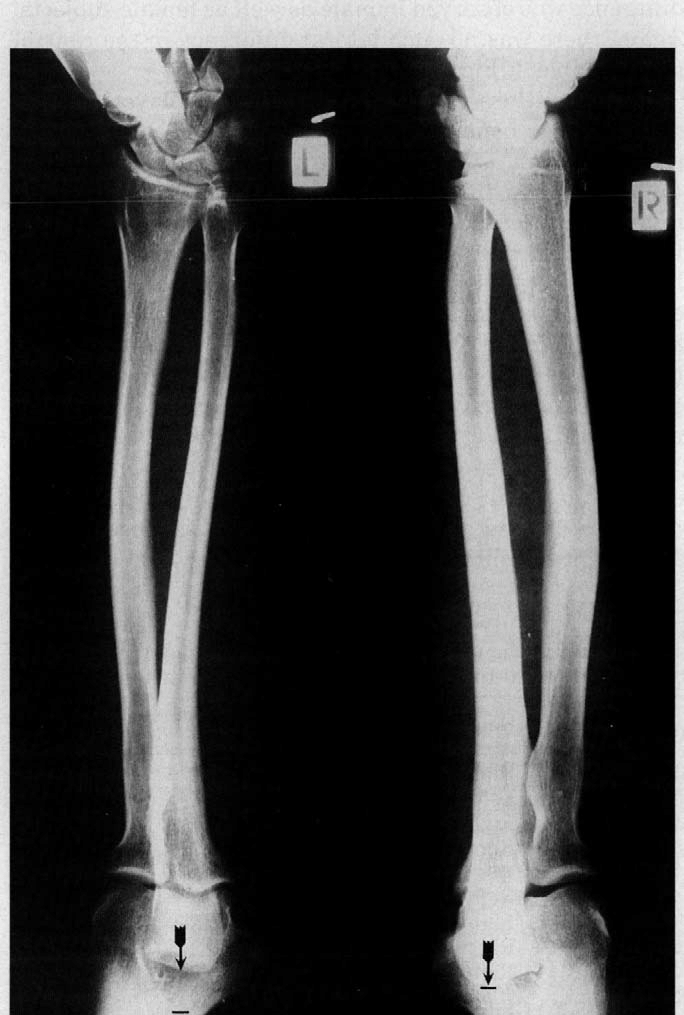

Tennis players have an 0.8mm longer forearm on the side they hold their racket with. On average, the dominant arm of tennis players is 3% longer than their non-dominant arm......